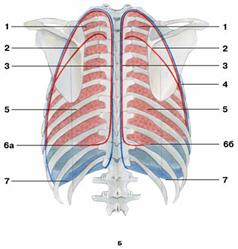

Рис. Границы легких

Рис. Границы легких

Б — вид сзади:

1 — верхняя доля;

2 — косая щель;

3 — задняя граница плевры;

4 — задний край правого легкого;

5 — нижняя доля;

6 — нижний край легкого: а) левого; б) правого;

7 — нижняя граница плевры